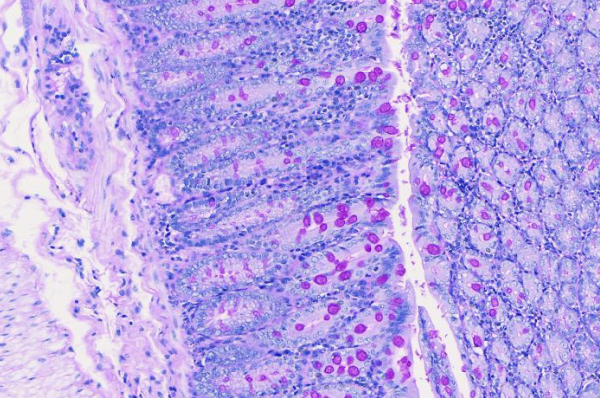

PAS染色

种属:小鼠 | 样本:肠